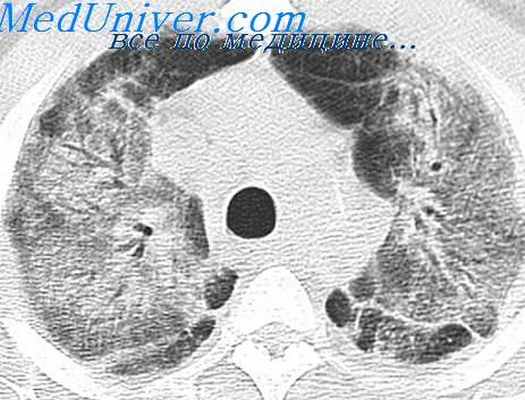

Острая эозинофильная пневмония - может быть идиопатической (без установленной причины), либо ассоциированной со СПИДом, приёмом медикаментов, ингаляцией бытовых и промышленных поллютантов (продукты жизнедеятельности человека токсического характера), табачного дыма. Чаще всего развивается у мужчин 20-30 лет. Характеризуется острым началом с лихорадкой, выраженной одышкой, кашлем без мокроты. В тяжёлых случаях возможно развитие дыхательной недостаточности. На рентгенограммах, на КТ легких определяется диффузная инфильтрация с обеих сторон. Эозинофилия в крови часто отсутствует, но всегда обнаруживается в БАЛ.

- диффузные инфильтративные изменения в обоих лёгких;

Болезнь характеризуется кашлем, повышением температуры тела, общей слабостью, похудением, иногда приступами удушья. В анализах крови определяются лейкоцитоз (до 50×10 9 клеток/л) и очень высокая эозинофилия (80—90 %). При рентгенологическом обследовании в лёгких обнаруживаются множественные мелкие тени, что напоминает картину милиарного туберкулёза. Лёгочные инфильтраты сохраняются долго, иногда в течение нескольких месяцев. Повышен титр холодовых агглютининов, часто положительная реакция Вассермана. Течение продолжительное, с периодическими обострениями.